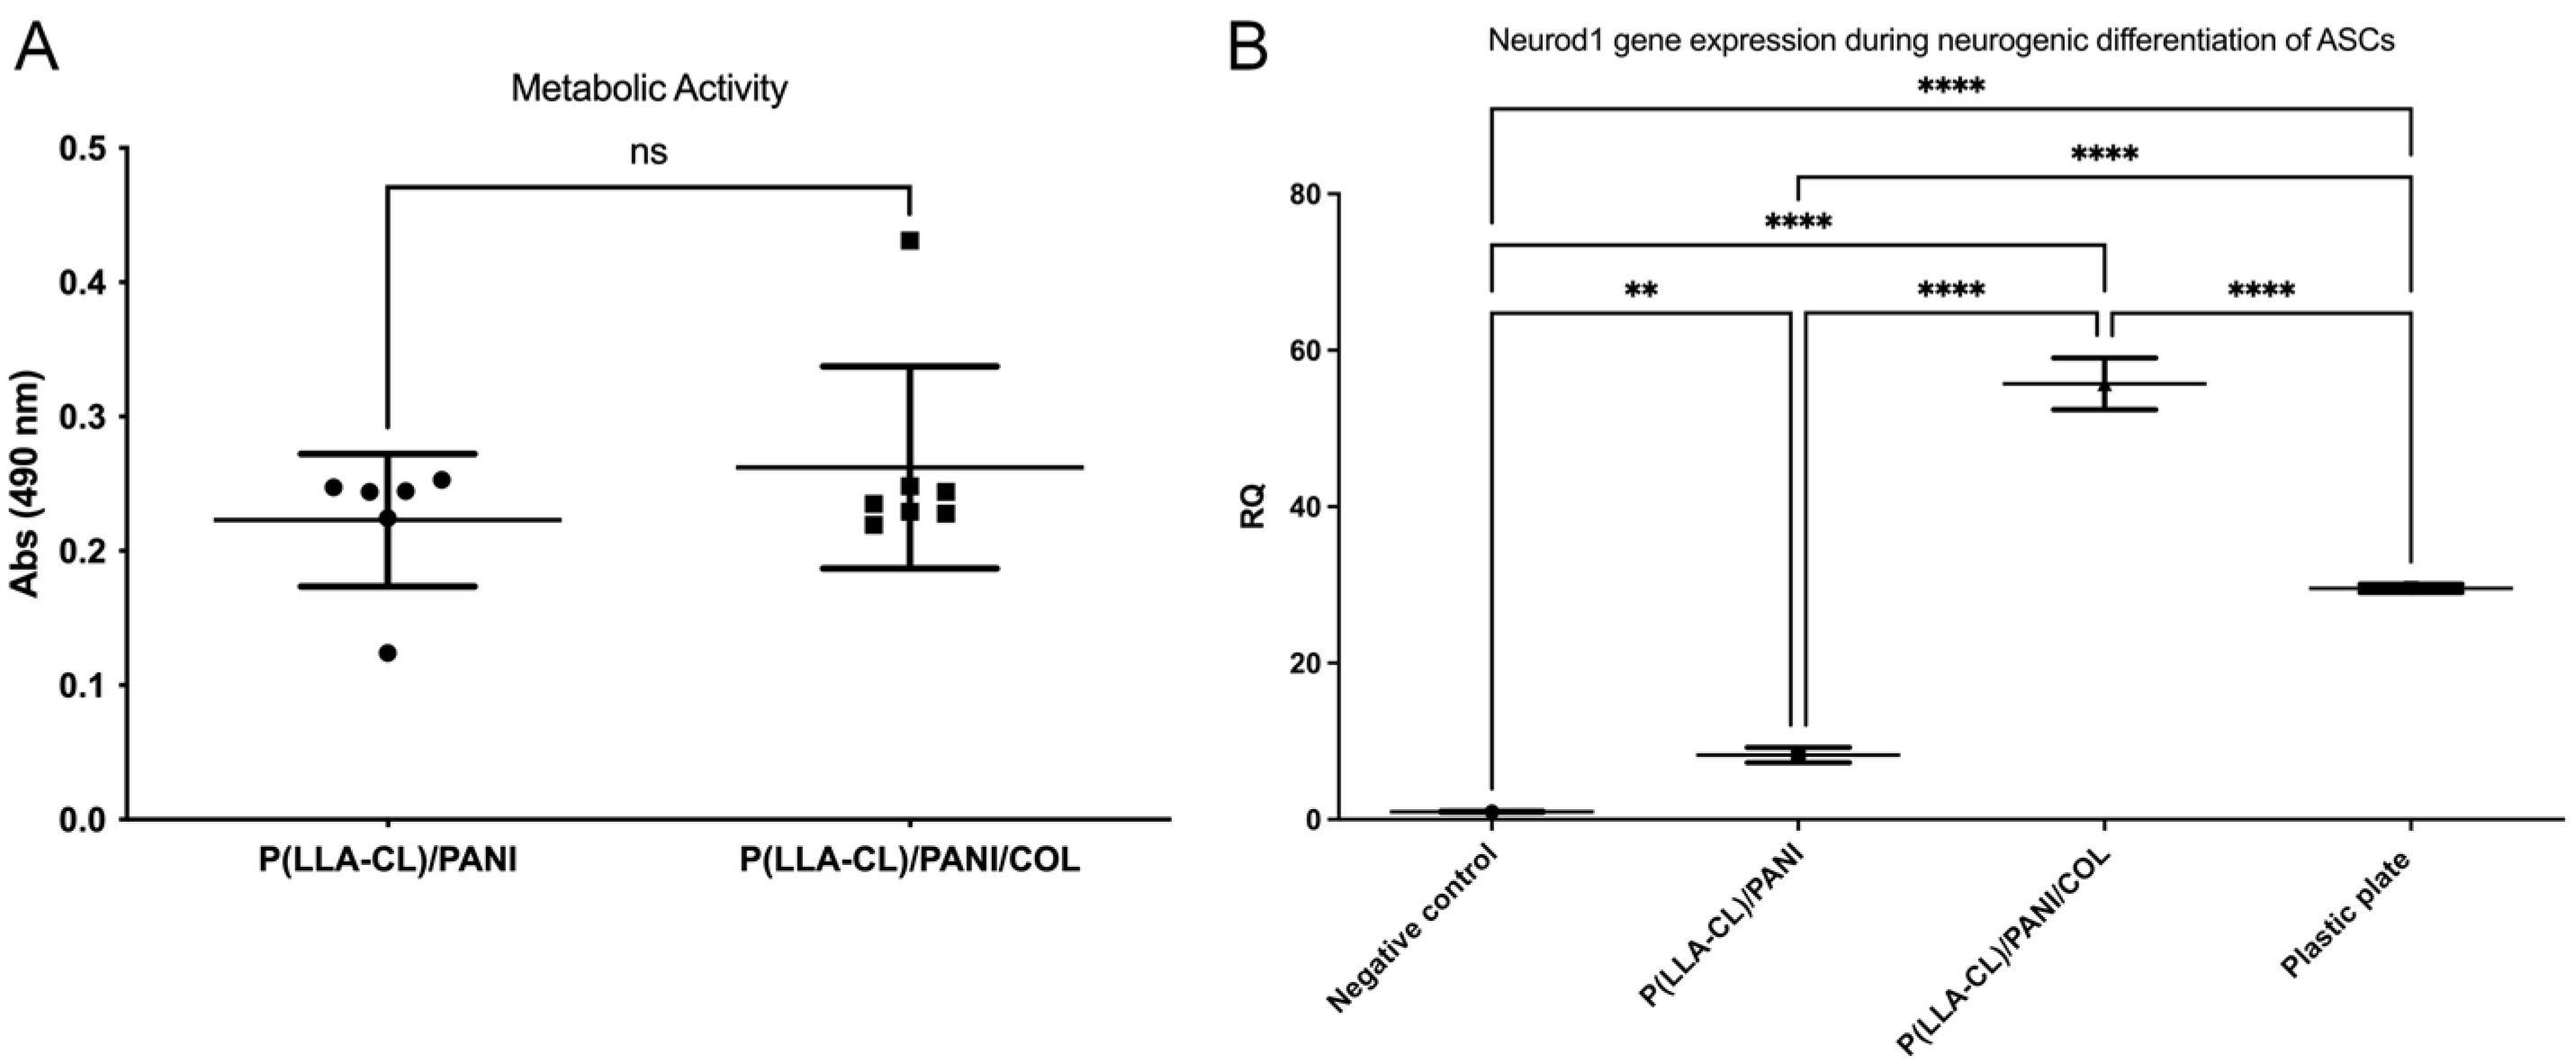

2.2. Biocompatibility Studies

4.4.2. Metabolic Activity of ASCs Cultured on P(LLA-CL)-COL-PANI and P(LLA-CL)/PANI Meshes

4.4.3. ASCs Neural Differentiation on P(LLA-CL)-COL-PANI and P(LLA-CL)/PANI Meshes